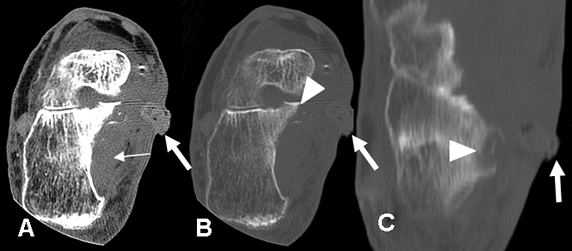

Fig 30 C. Osteomielitis aguda.

A y B: TAC axial. C: TAC reconstrucción coronal. Igual paciente anterior. Mala evolución clínica, con fiebre y sepsis. En el TAC de control se encuentra osteolisis del arco anterior y el lado derecho de C1 y la odontoides, por osteomielitis. (Puntas de flecha). Hay fragmentos óseos libres dentro del canal. (Flechas delgadas). Adicionalmente existen burbujas de aire dentro del canal, por la formación de absceso. (Flechas gruesas).